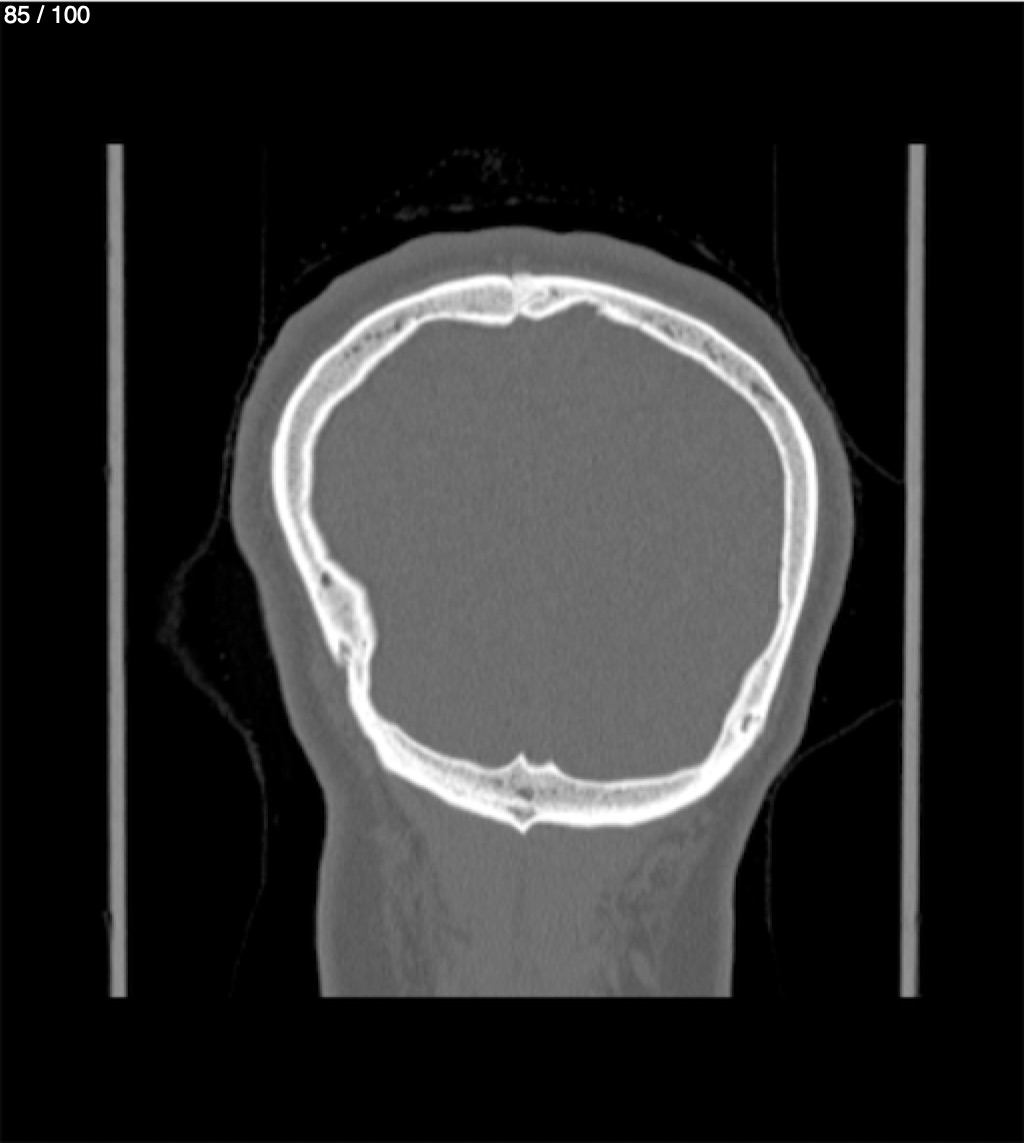

Yonelly Barrios Diaz 35A - T.C Craneo